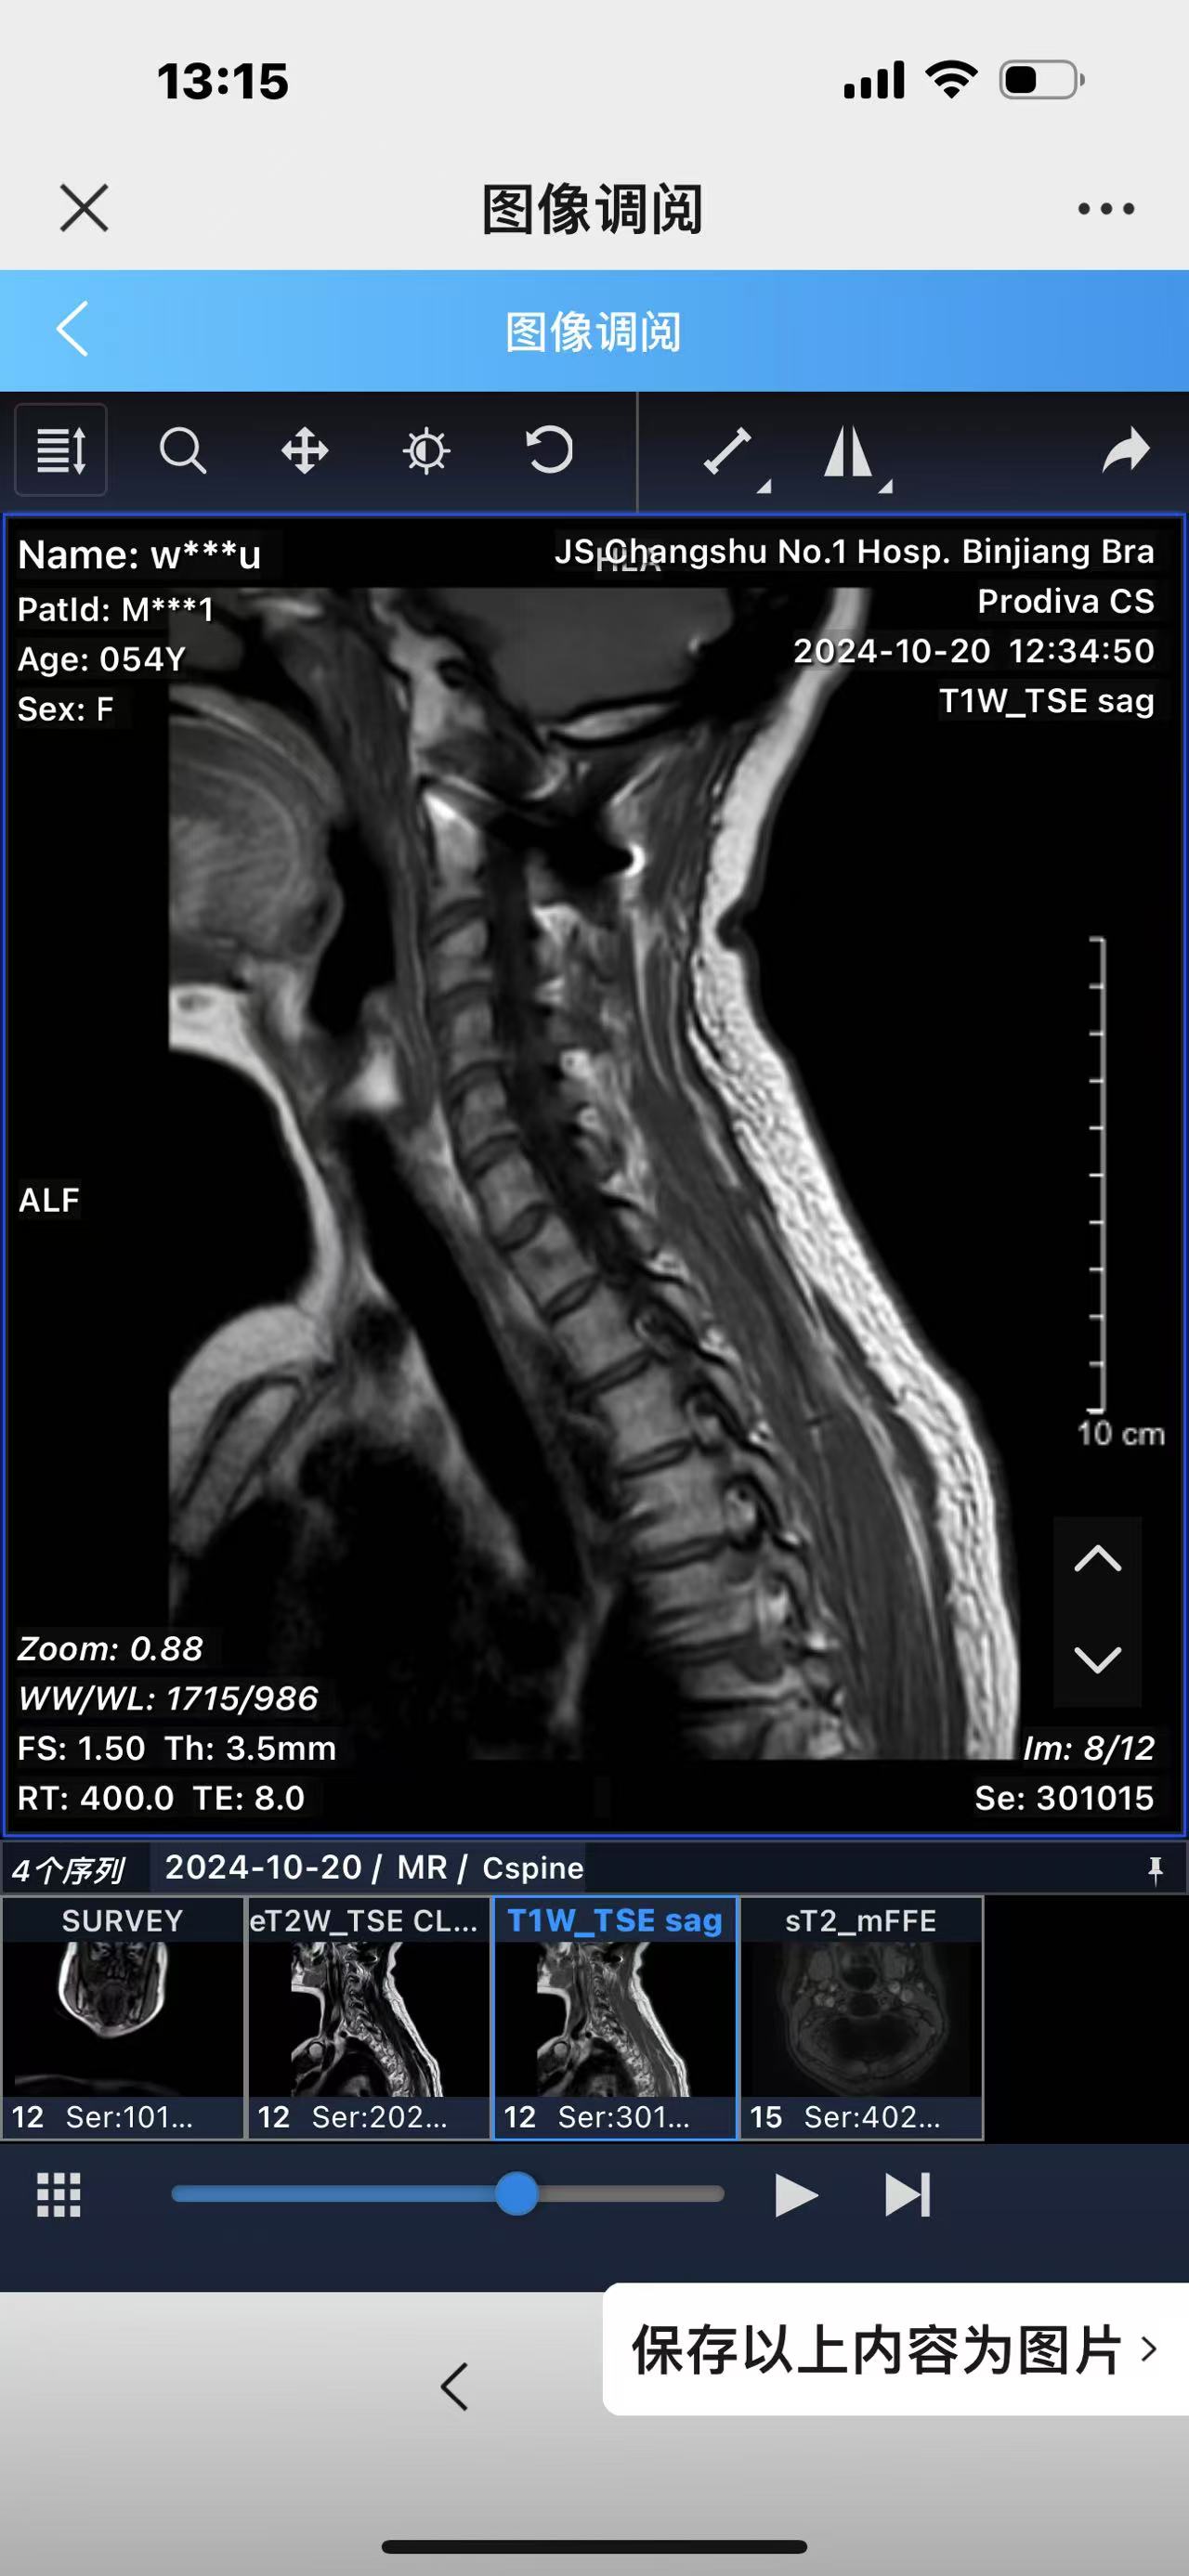

• 诊断:寰枢椎脱位,颅底凹陷

• 术后影像:

• 2024.02.27,复查,对位良好,偶尔会肩甲骨酸,坐下就不酸。

• 2024.10.20,复查,对位良好,偶尔会肩甲骨酸,坐下就不酸。